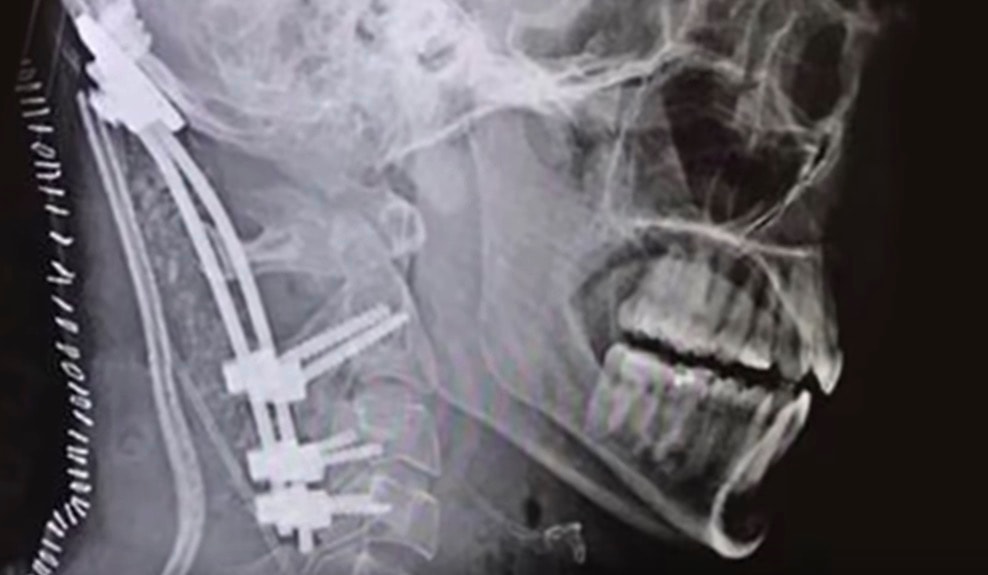

Pacjentowi wszczepiono płytkę, specjalne pręty i śruby do połączenia i stabilizowania czaszki i kręgosłupa. Kolejnym etapem jest w takich przypadkach wielomiesięczna rehabilitacja. Obecnie pacjent ma problemy z poruszaniem prawą ręką oraz cierpi na bóle dolnych kończyn.